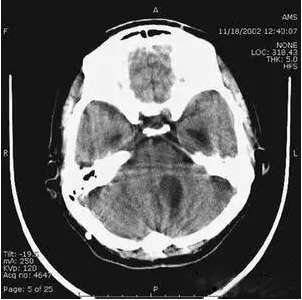

(機器故障偽影:常為環(huán)形或同心圓狀高密度偽影)

部分容積效應(yīng)偽影的形狀可因物體的不同而不一樣,一般在重建后橫斷面圖像上可見條形、環(huán)形或大片干擾的偽像。最常見和典型的現(xiàn)象是在頭顱橫斷面時的顳部出現(xiàn)的條狀偽影,又稱哼氏偽影。該偽影現(xiàn)象可采用薄層掃描而減弱;在西門子系列的CT機中.用VAR掃描技術(shù)可抑制該偽影。